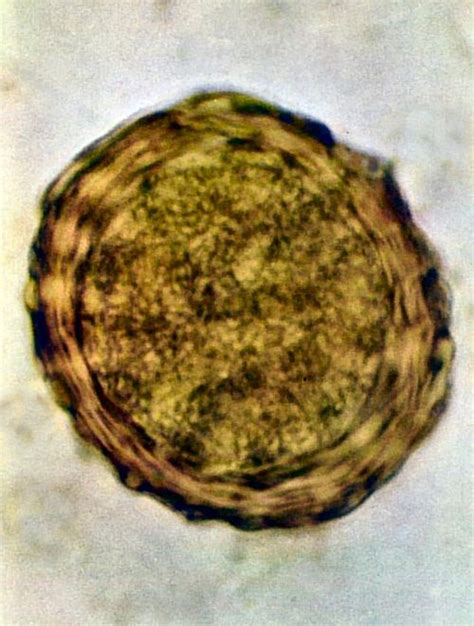

- Cytologické vyšetrenie (stier z ucha): Z postihnutého ucha sa odoberie vzorka výtoku vatovým tampónom. Tento vzorka sa následne nanesie na sklíčko, zafarbí a prezrie pod mikroskopom. Cytológia pomáha identifikovať prítomnosť a množstvo baktérií, kvasiniek, zápalových buniek alebo parazitov (napr. ušný svrab).

- Ušný svrab: Je spôsobený mikroskopickými parazitmi zvanými Otodectes cynotis, ktorí žijú na povrchu kože vo zvukovode a živia sa ušným mazom a odumretými kožnými bunkami. Napadnutie týmito parazitmi je vysoko nákazlivé, najmä medzi šteniatkami a mačkami. Typickým príznakom je intenzívne svrbenie, ktoré núti psa k neustálemu škriabaniu uší a traseniu hlavou. V ušiach sa tvorí charakteristický tmavohnedý až čierny, suchý, drobivý výtok, ktorý môže pripomínať kávovú usadeninu.